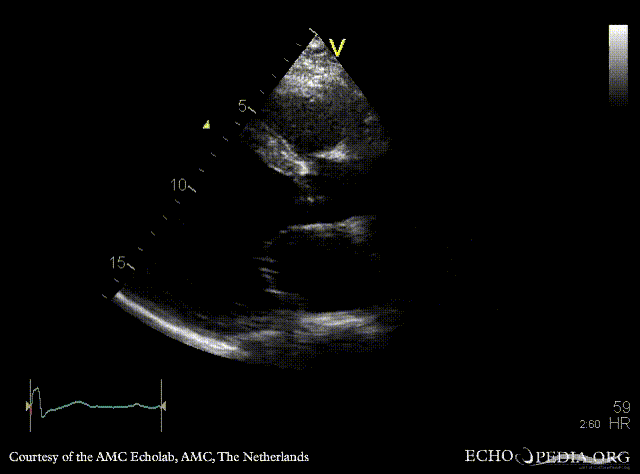

| Courtesy of: AMC Echolab, AMC, The Netherlands | |

| PLAX: Dilated left ventricle with poor function | A4CH |